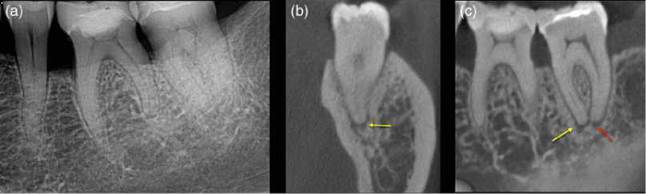

Figure 6.14 Condensing osteitis. (a) Periapical radiograph and (b) sagittal CBCT scan reveals increased radiopacity associated with the mesial root of the mandibular molar tooth, a sign of reactive osteosclerosis (yellow arrow) due to chronic irritation in the 46.

Figure 6.16 Apical periodontitis. (a) Radiograph of lower left quadrant in patient with poorly localized symptoms of irreversible pulpitis. (b, c) coronal and sagittal reconstructed CBCT views confirm a periapical radiolucency associated with the mesial (yellow arrow) and distal (red arrow) roots of the lower left second molar tooth.

Figure 6.18 Vertical root fracture. (a) A periapical radiograph of the lower right molar teeth does not reveal anything untoward, however, the (b) sagittal (red arrows) and (c) axial (yellow arrow) CBCT slices reveal a clear radiolucency associated with the mesial root.